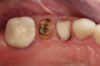

Fig 14. Final impression and cast.

Figure 14

Fig 15. Provisionals 12 weeks postoperatively.

Figure 15

After the preparations were evaluated and accepted by the clinician, provisionals were completed with traditional crown-and-bridge techniques. Then the provisionals were fabricated with a replication stent derived from the diagnostic wax up (Figure 14). The provisionals were well-fitted to both the natural dentition and the ceramic dental implants (Figure 15). The provisional that was fixed to the implant was kept out of occlusion and had a narrow buccal-lingual occlusal table. The smaller occlusal table and short occlusal scheme provided light loading forces and stimulated the bone tissuethe brain detects the stimuli and sends osteoblasts to the area to increase bone density surrounding the implant. The recommendation for the light-loading provisional phase was to have the patient function with the provisionals for 4 weeks.